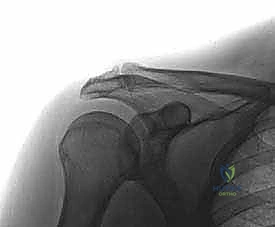

2. التصوير الطبي المتقدم (Medical Imaging)

- الأشعة السينية (X-rays): يتم أخذ صور بوضعيات خاصة (مثل Zanca view) لتقييم المفصل بدقة، حيث تظهر تضيق المسافة المفصلية، التصلب العظمي (Sclerosis)، والنتوءات العظمية، أو التكيسات العظمية (في حالات رافعي الأثقال).

- التصوير بالرنين المغناطيسي (MRI): يُعد أداة حاسمة ليس فقط لتقييم درجة تلف الغضروف والتهاب نقي العظم في الترقوة، ولكن الأهم من ذلك، لاستبعاد أي تمزقات مرافقة في أوتار الكفة المدورة، والتي تتواجد بشكل متزامن في نسبة كبيرة من المرضى.